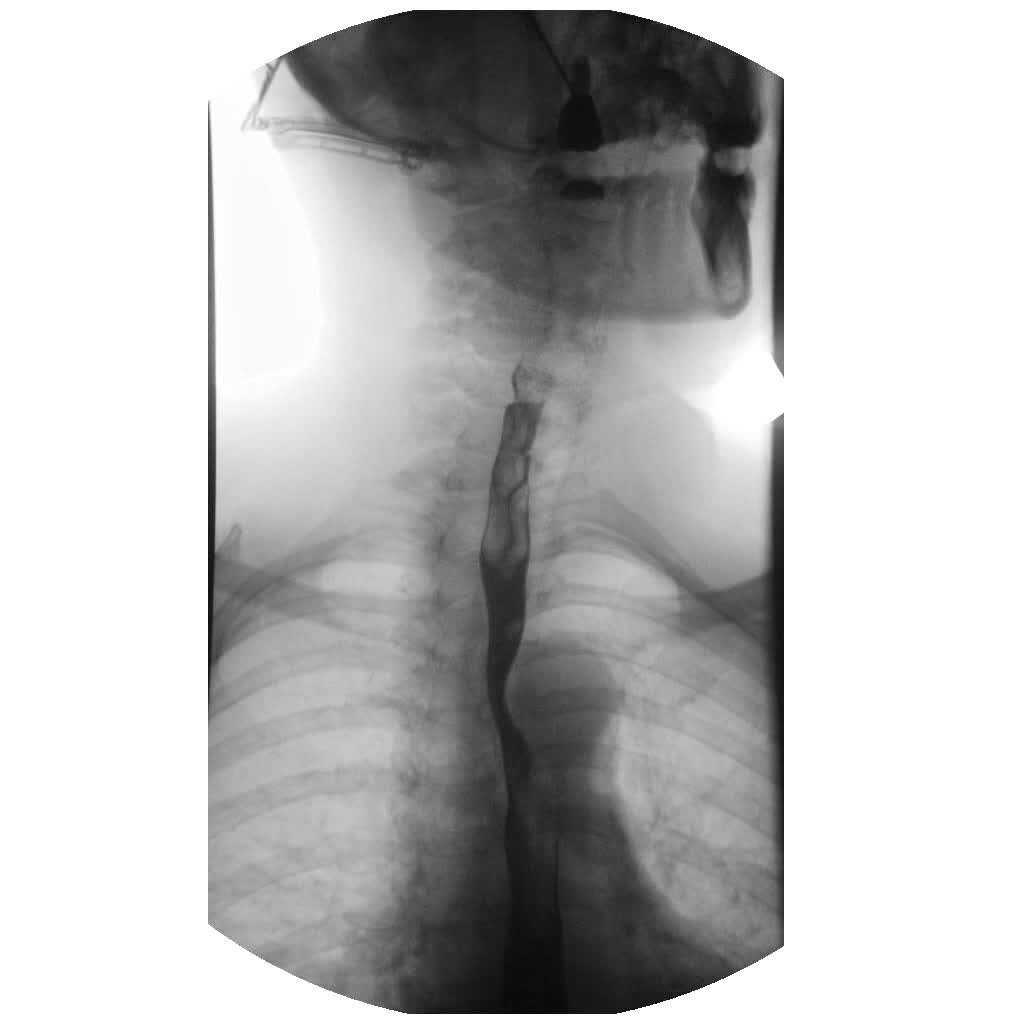

Here is an example of a normal barium swallow study, in which the barium (the dark liquid) is seen moving down the esophagus without any leakage or regurgitation (reflux):

Share on Pinterest

Photo: Anka Friedrich / commons.wikimedia.org